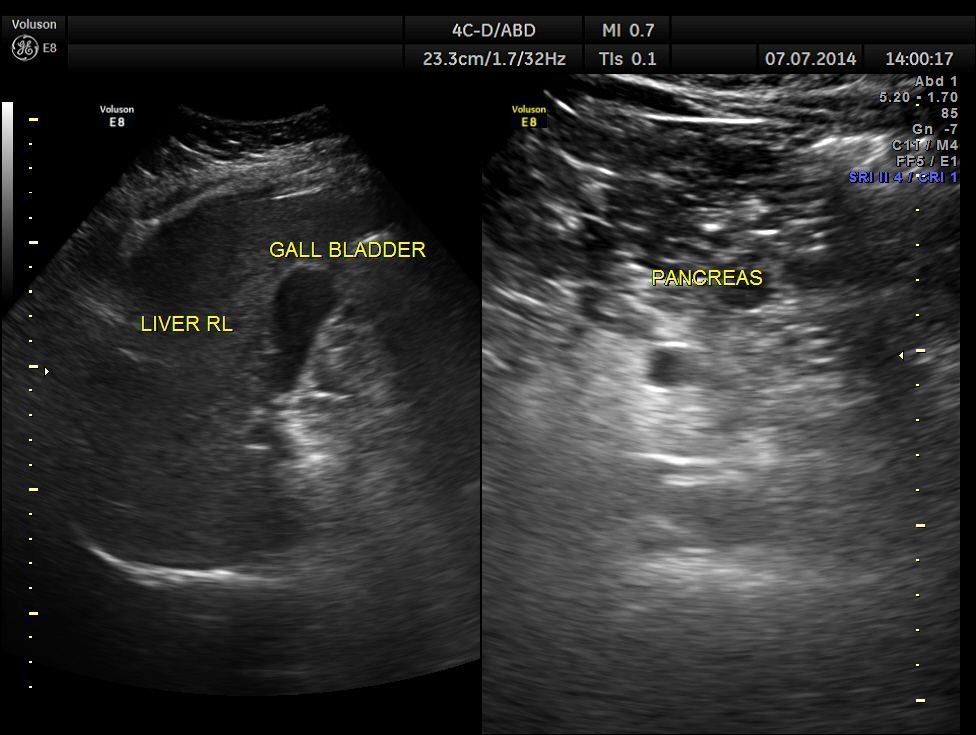

His ultrasound showed the following :